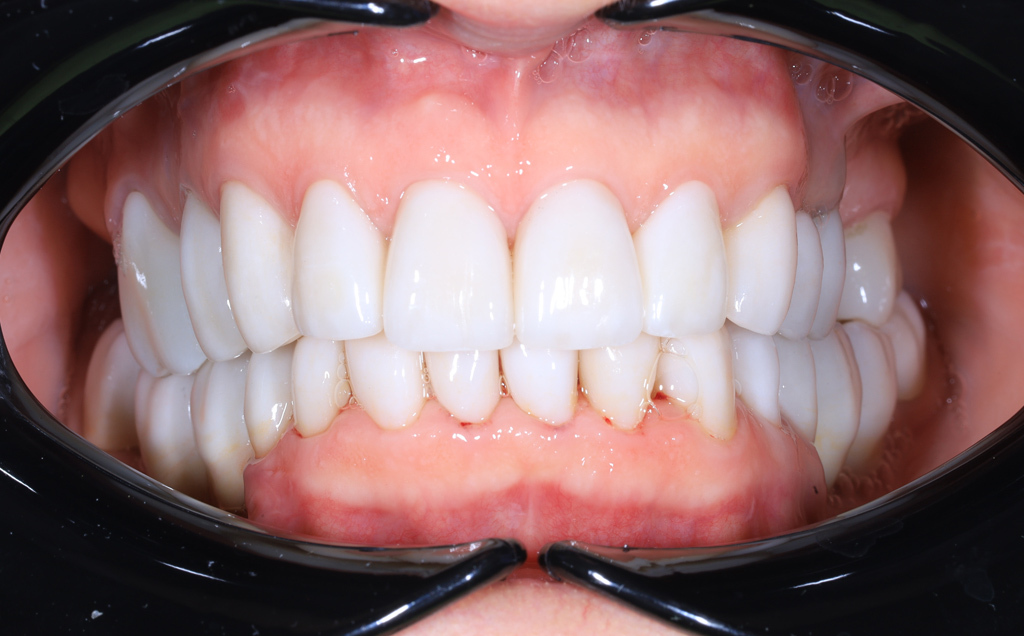

Zaprezentujemy serię poruszających historii pacjentów, którzy zdecydowali się na kompleksowe leczenie dentystyczne. Od przypadków zaawansowanej próchnicy, przez wypadki, które wymagały rekonstrukcji zębów, po pacjentów marzących o hollywoodzkim uśmiechu dzięki zastosowaniu licówek – każda historia jest dowodem na to, jak nowoczesna stomatologia może odmienić życie.

Skupimy się na innowacyjnych technologiach i metodach leczenia stosowanych w naszej klinice, które sprawiają, że te metamorfozy są możliwe. Od cyfrowego projektowania uśmiechu (DSD), przez ortodoncję i implanty, po zaawansowaną chirurgię szczękowo-twarzową. Omówimy, jak te techniki pracują razem, aby osiągnąć najlepsze wyniki.

Poprawa estetyki uśmiechu: wybielanie zębów.